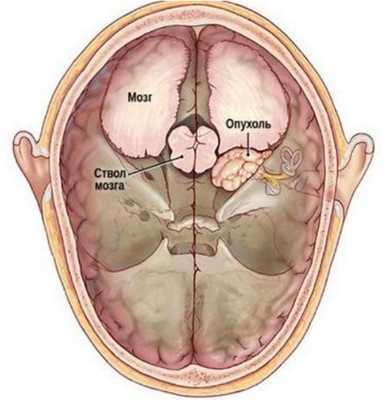

Наиболее частая локализация опухоли — у входа во внутренний слуховой проход на концевой части слухового нерва. Поскольку слуховой нерв вместе вестибулярным и двигательным лицевым нервом нерв входят в единый внутренний слуховой проход на основании черепа, то увеличение опухоли сдавливает все прилежащие нервы, вызывая типичную клиническую симптоматику (рис. ниже).

Патогенез

При росте в мостомозжечковый угол после достижения размера 1,5 см в диаметре, она начинает воздействовать (сдавливать) на латеральные поверхности ствола мозга, вызывая смещение в контралатеральную сторону ствола мозга. При достижении размера 2 см опухоль оказывает давление в направлении вверх/вперед, вызывая компрессию тройничного нерва, что проявляется нарушением чувствительности на соответствующей половине лица/снижением роговичного рефлекса. Опухоль в мостомозжечковом углу при размере в 4 см воздействует на IV желудочек/сильвиев водопровод с постепенным развитием окклюзионной гидроцефалии.